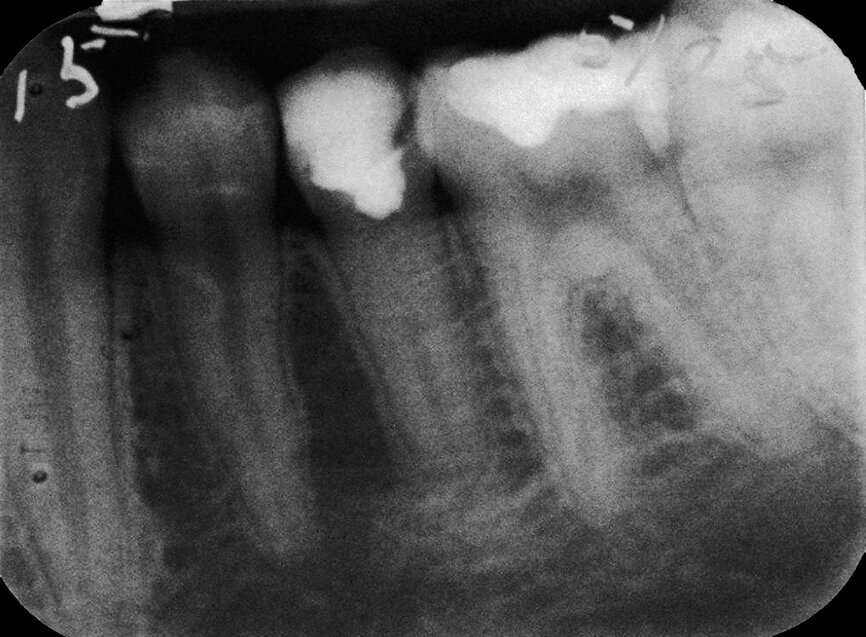

Case 1: Male (born 5 June 1987): Tooth 35

Fig. 3a: 18 March 1997 ante pulpotomy.

Fig. 3b: 18 March 1997 post pulpotomy

Fig. 3c: 6 May 2005 status